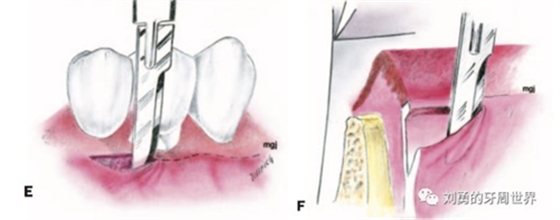

3、用15號刀片,在受區(qū)膜齦聯(lián)合的位置從遠中向近中做半厚切口,刀片平行于骨面(E和F)

4、刀片按照受區(qū)的近遠中長度完成初始的半厚瓣全長切口

5、刀片向根向繼續(xù)分離半厚瓣,冠根向延伸6-8mm,注意避讓頦神經(jīng),翻開半厚瓣如下圖: